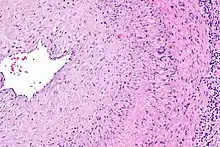

Biopsy

The gold standard for diagnosing temporal arteritis is biopsy, which involves removing a small part of the vessel under local anesthesia and examining it microscopically for giant cells infiltrating the tissue.[23] However, a negative result does not definitively rule out the diagnosis; since the blood vessels are involved in a patchy pattern, there may be unaffected areas on the vessel and the biopsy might have been taken from these parts. Unilateral biopsy of a 1.5–3 cm length is 85-90% sensitive (1 cm is the minimum).[24] Characterised as intimal hyperplasia and medial granulomatous inflammation with elastic lamina fragmentation with a CD 4+ predominant T cell infiltrate, currently biopsy is only considered confirmatory for the clinical diagnosis, or one of the diagnostic criteria.[11]